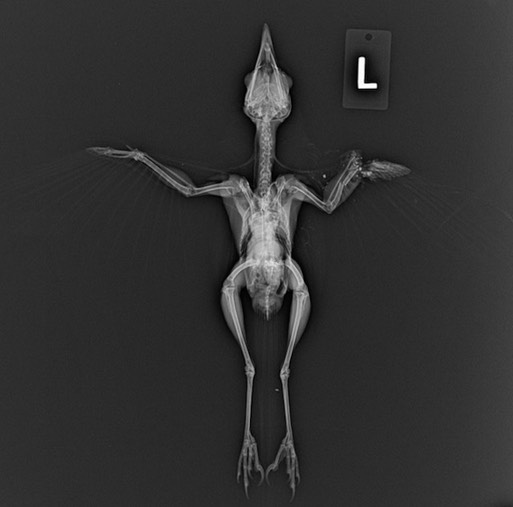

Red-tailed Hawk 22-091

22-091 was found trapped in a culvert. An exam and x-rays revealed fractures in the right scapula and right minor metacarpal as well as a brood patch. Because it is still fairly early, the hawk was likely incubating eggs rather than nestlings. We are hopeful she will make a full recovery.